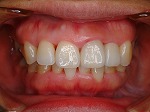

◆オールセラミック修復

~修復前~

オールセラミック修復

~修復後~